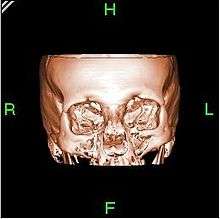

Three-dimensional reconstruction

Because contemporary CT scanners offer isotropic or near isotropic resolution, display of images does not need to be restricted to the conventional axial images. Instead, it is possible for a software program to build a volume by "stacking" the individual slices one on top of the other. The program may then display the volume in an alternative manner.[58]

3D rendering techniques

Surface rendering

A threshold value of radiodensity is set by the operator (e.g., a level that corresponds to bone). From this, a three-dimensional model can be constructed using edge detection image processing algorithms and displayed on screen. Multiple models can be constructed from various thresholds, allowing different colors to represent each anatomical component such as bone, muscle, and cartilage. However, the interior structure of each element is not visible in this mode of operation.

Volume rendering

Surface rendering is limited in that it will display only surfaces that meet a threshold density, and will display only the surface that is closest to the imaginary viewer. In volume rendering, transparency, colors and shading are used to allow a better representation of the volume to be shown in a single image. For example, the bones of the pelvis could be displayed as semi-transparent, so that, even at an oblique angle, one part of the image does not conceal another.